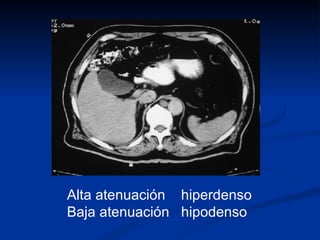

Este documento presenta términos relacionados con la imagen médica y su interpretación. Define pares de términos opuestos que describen las propiedades de los tejidos y órganos en radiografías, tomografías computarizadas y ecografías, como radiopaco/radiolúcido, hiperdenso/hipodenso, hipertensa/hipointensa, y hipercaptante/hipocaptante.